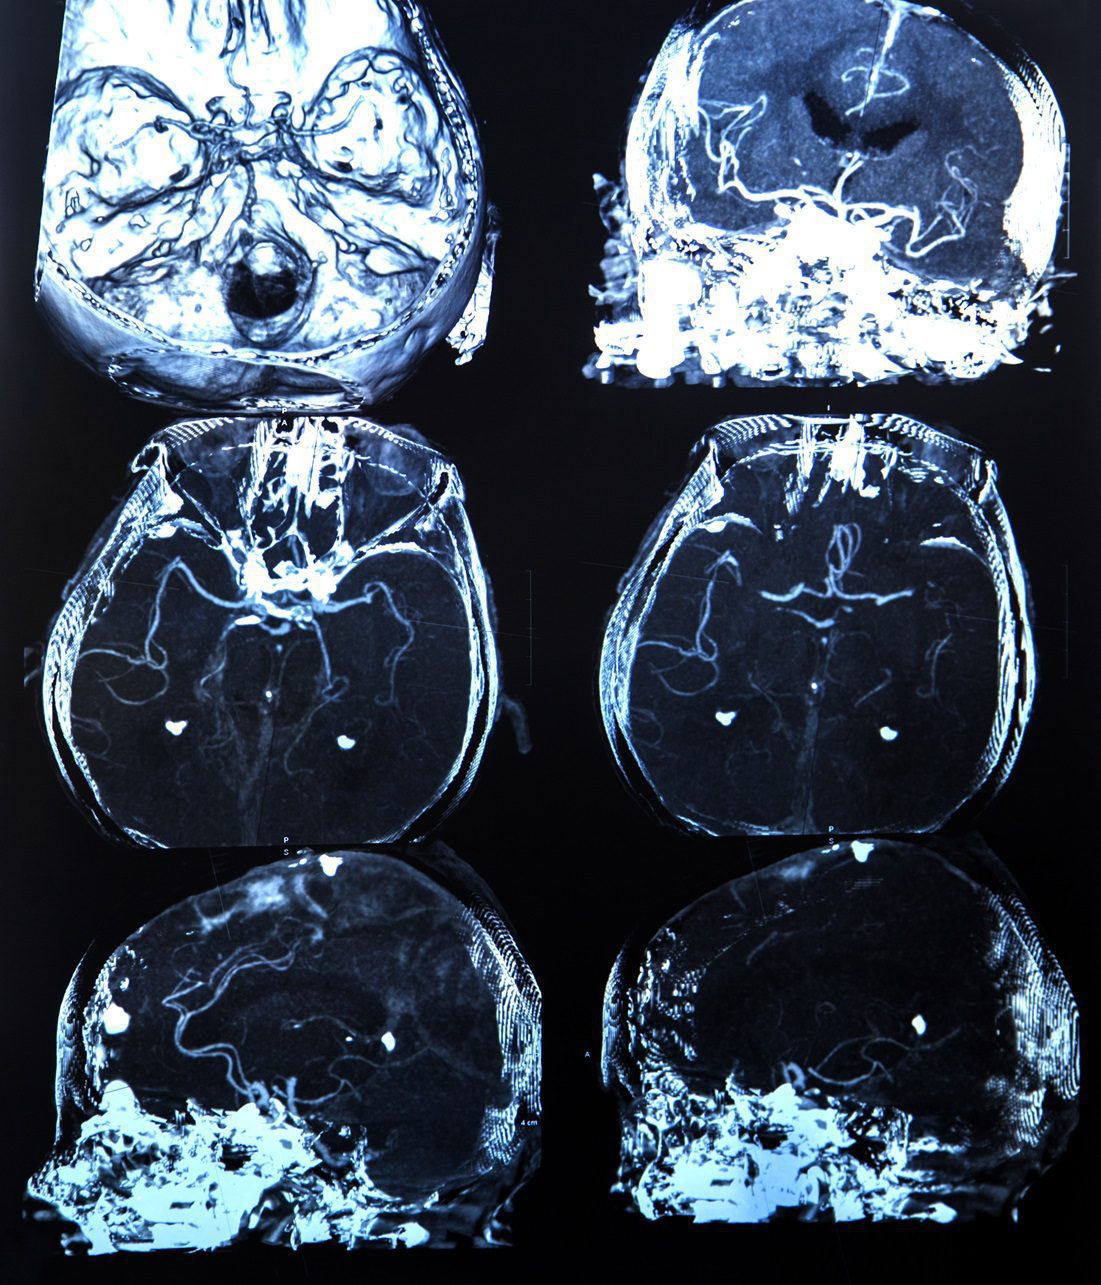

- Magnetic resonance imaging (MRI): This is the most commonly used tool to detect demyelinating lesions in the brain and spinal cord. MRI scans can reveal areas where myelin has been damaged.